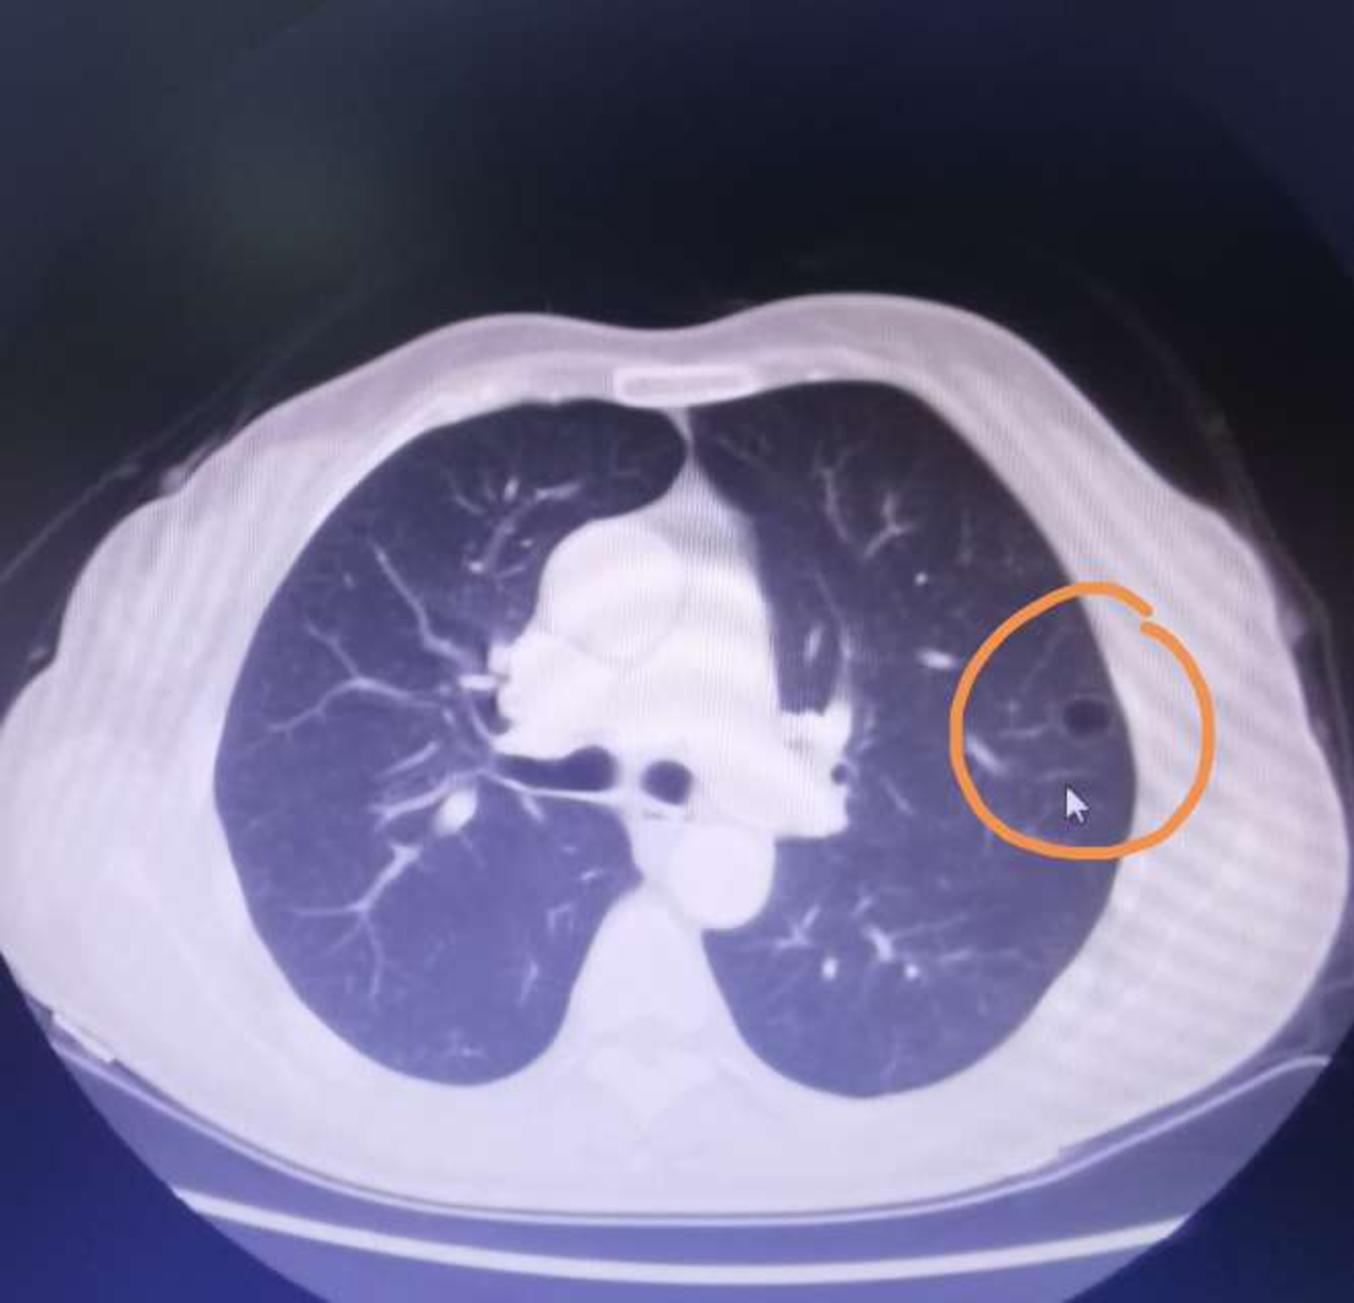

11):这个肺结节伴空腔我判断为良性可能性大-空腔征在实性结节中的

图片尺寸849x660